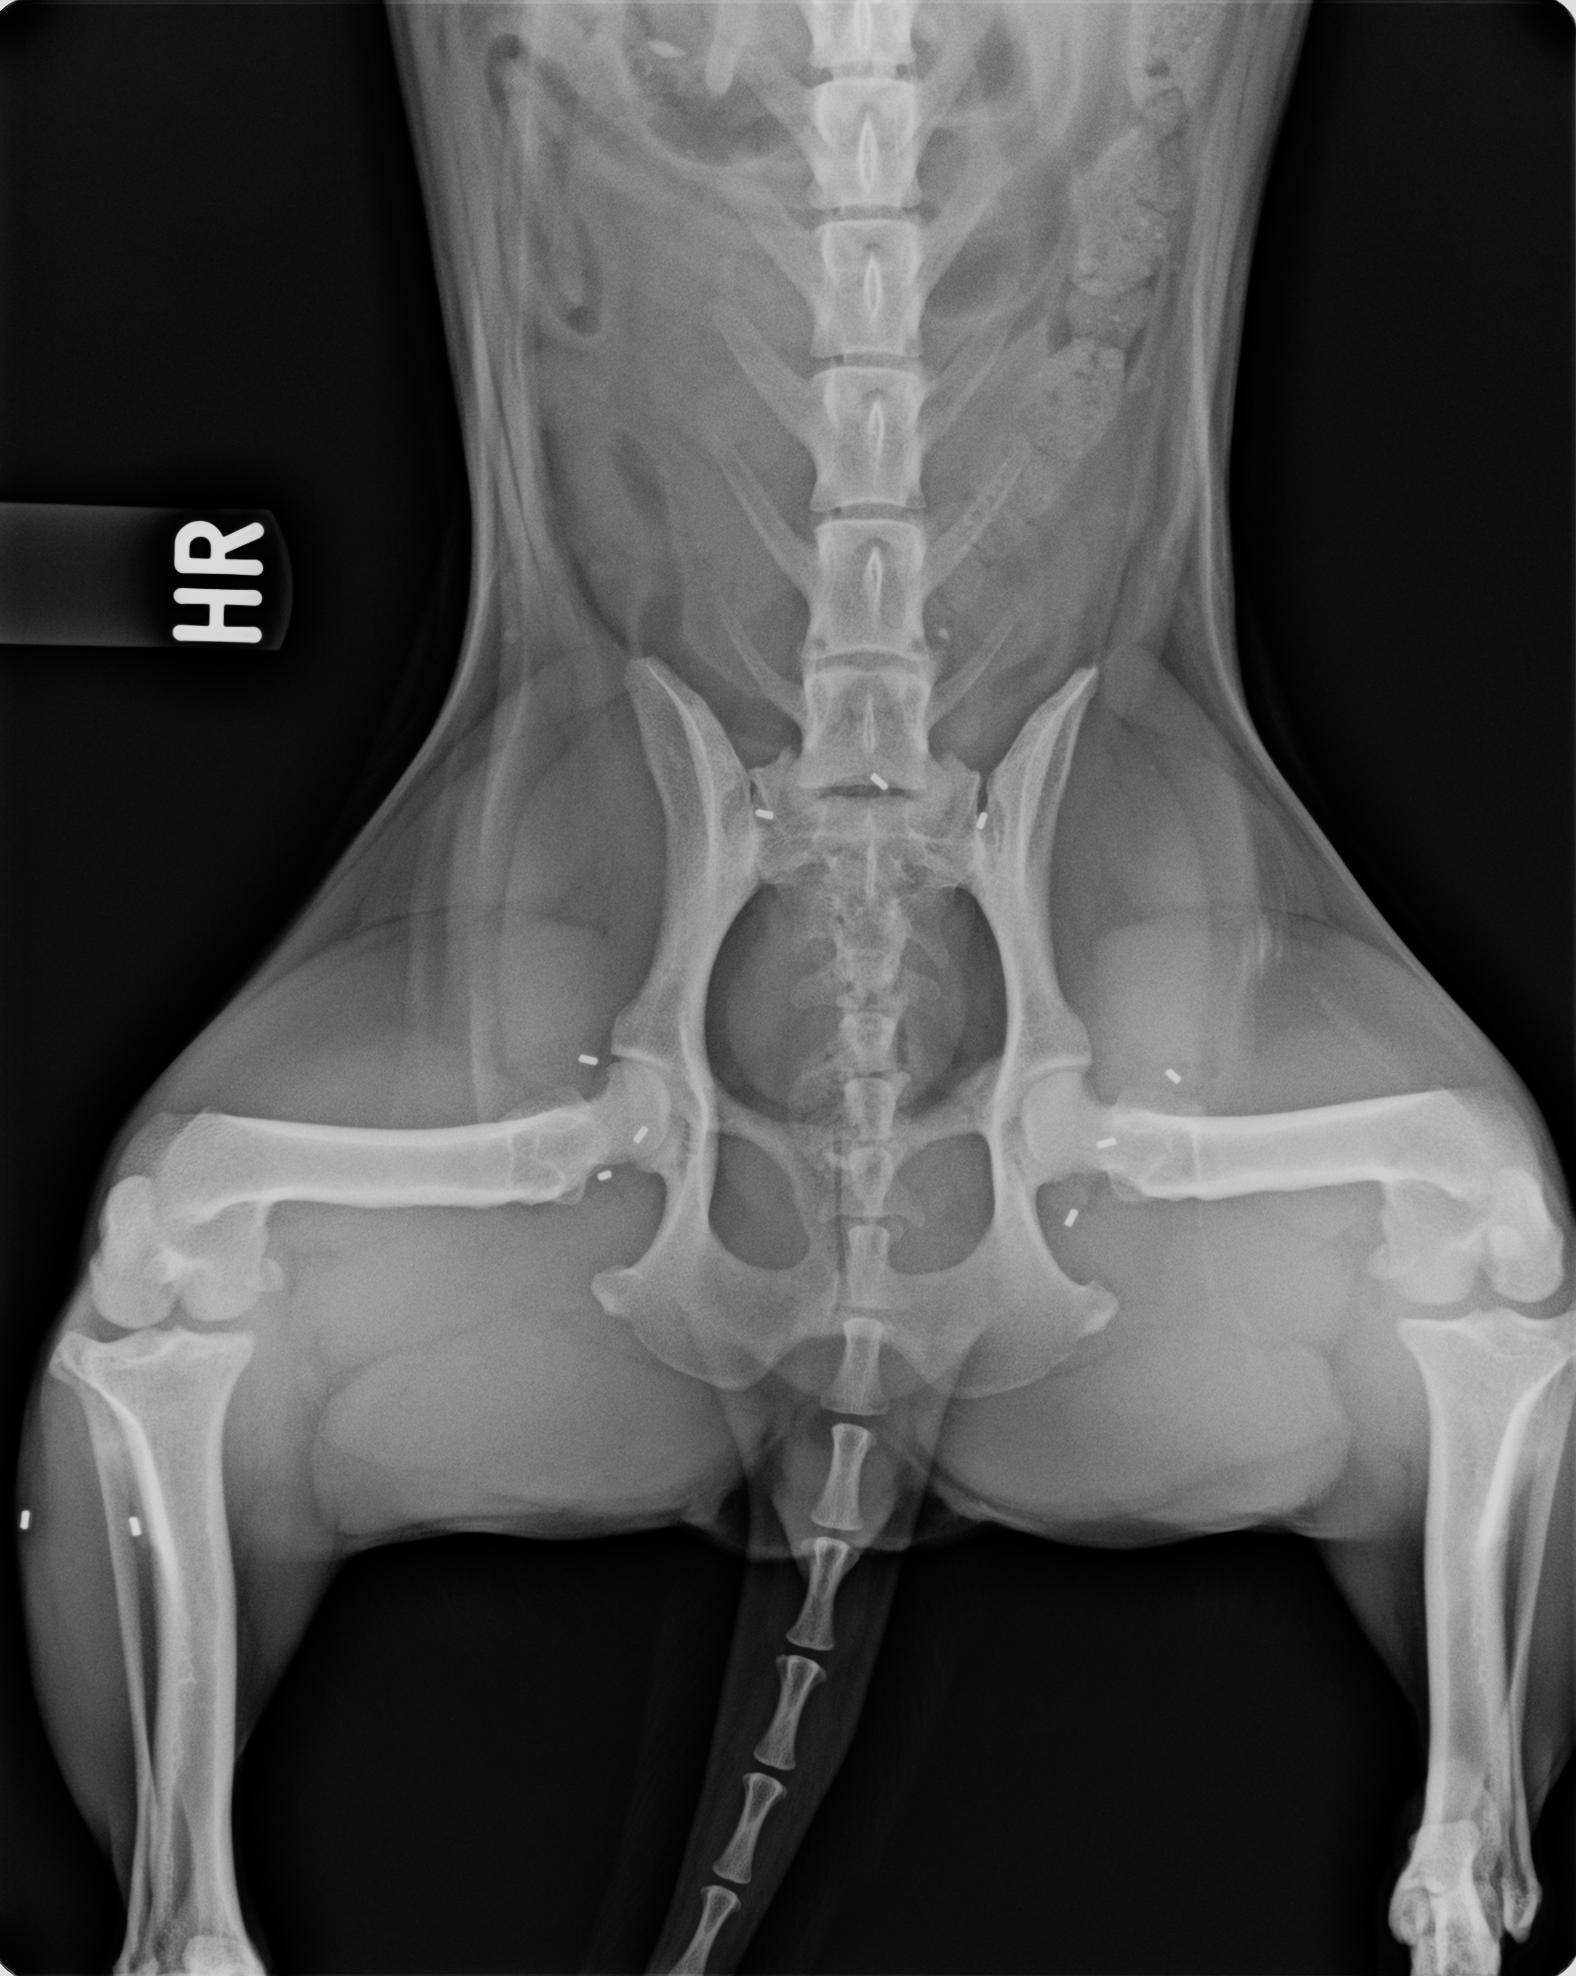

Das „A und O“ jeder Therapie ist die Gewissenhaftigkeit der Diagnostik. Sie fängt bereits bei der Vorberichtserhebung an. Ausführliche Gangbildanalysen und Schmerzpunkt-Untersuchungen sind genauso unerlässlich wie der Einsatz geeigneter, bildgebender Verfahren wie auch bei Bedarf Labordiagnostik. Hier müssen wir entscheiden, ob man Röntgenbilder anfertigt, Ultraschalldiagnostik betreibt, oder sogar CT- oder MRT-Aufnahmen benötigt. Herz und Kreislauf werden auf Narkosefähigkeit geprüft. Sobald man sich vor dem Hintergrund mittlerweile jahrzehntelanger Erfahrung für die Methode der Goldakupunktur entscheidet, kommt das Spezialwissen der Traditionellen Chinesischen Medizin und der Akupunktur auf den Plan. Auf Basis der westlich-wissenschaftlichen Erkenntnisse um Schmerz und Biomechanik auch unter Zuhilfenahme verschiedener z.B. pulsdiagnostischer Verfahren wird der der Akupunktur-Kontext ermittelt. Daraufhin wird ein Implantationsprotokoll. Dieses bezieht auch unter Umständen weitere, bestehende Leiden mit ein, wie z.B. Anfallsleiden, innere Erkrankungen, neurologische Erkrankungen oder Funktionsstörungen wie Inkontinenz.

Häufig wird ein Termin vereinbart, zu welchem nach den vorher durchgeführten Untersuchungen im wachen Zustand, die Diagnostik wie z.B. Röntgen unter Sedation (Leichtnarkose) erfolgt. Zur Vermeidung weiterer, unnötiger Narkosen kann die Behandlung direkt im Anschluss an die Diagnostik durchgeführt werden. Natürlich muss geklärt werden, dass andere therapeutische Optionen nicht Vorrang haben. Die Goldimplantate werden nach sorgfältiger Reinigung der Behandlungsareale entweder durch Hohlnadeln und / oder Injektionstechnik an die Akupunkturpunkte gesetzt. Nach dem Aufwachen spüren die Patienten diese Implantate in der Regel nicht. Begleitende, schmerzhaftere Eingriffe wie Gelenksinjektionen werden unter zeitgleicher, medikamentöser Schmerztherapie und unter antibiotischem Schutz unter ebenso chirurgisch sterilen Bedingungen durchgeführt.

Die Goldakupunktur ist wie jede andere Therapieart kein „Alleskönner“! Sie hat sich aber seit Jahrzehnten als Schmerztherapie bei folgenden Krankheiten bewährt: Hüftgelenksdysplasie, Hüftgelenksarthrosen, Arthrosen der Ellenbögen, Schultergelenke, Kniegelenke, Sprunggelenke, Vorderfußwurzelgelenke wie der Zehengelenke, bei Wirbelsäulenleiden bis hin zu neurologischen Begleiterkrankungen wie z.B. auch dem Cauda Equina Compressions Syndrom. Häufig können wir erreichen, dass die meisten Patienten über lange Zeit frei von Schmerzmitteln bei guter Lebensqualität aktiv am Leben teilnehmen können.